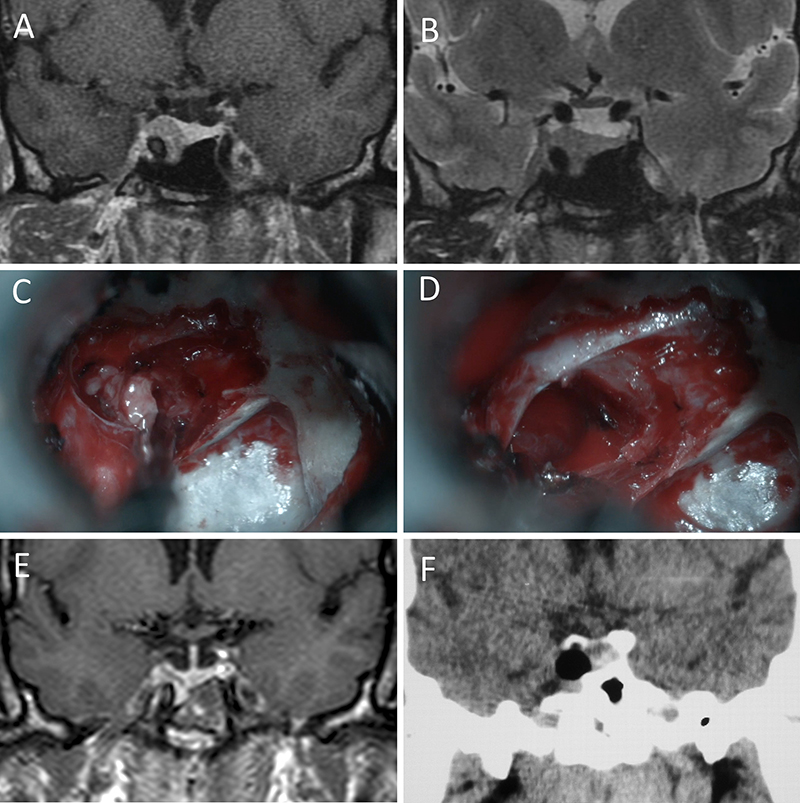

Figura 5: Apoplejía hipofisaria hemorrágica en un hombre de 32 años. El paciente presentó cefalea y parálisis completa del III par. Tuvo restitutio ad integrum en el seguimiento. A-B: RM preoperatoria; C-D: intraoperatorio; E-F: RM postoperatoria.

Figura 6: Apoplejía hipofisaria hemorrágica en un hombre de 55 años. El paciente presentó cefalea, déficit visual y parálisis completa del III par. Evolucionó favorablemente tras la cirugía, revirtiendo el cuadro. A-B: RM preoperatoria; C-D: intraoperatorio; E-F: RM postoperatoria.